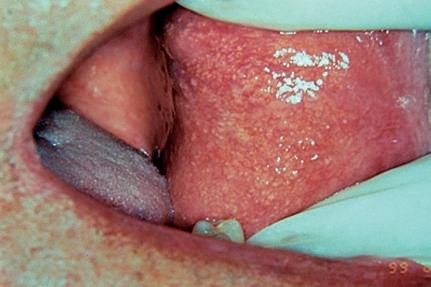

Manchas

São alterações de cor da mucosa ou pele, uniformes e sem relevo, podendo variar desde colorações mais claras, brancas até as mais enegrecidas, amarronzadas e arroxeadas, dependendo do tipo de pigmento. Não apresentam tamanho definido, podem ser puntiformes ou atingirem alguns centímetros (Fig. 1-1).

Exemplos: melânicas (pigmentos endógenos [Fig. 1-2], e exógenos [Fig. 1-3]), hemáticas (vasculares e hemorrágicas [Fig. 1-4]).

Vale lembrar que, classicamente, para as manchas secundárias devemos denominá-las de mácula, como por exemplo as manchas melânicas (Fig. 1-5) e eritematosas após trauma.